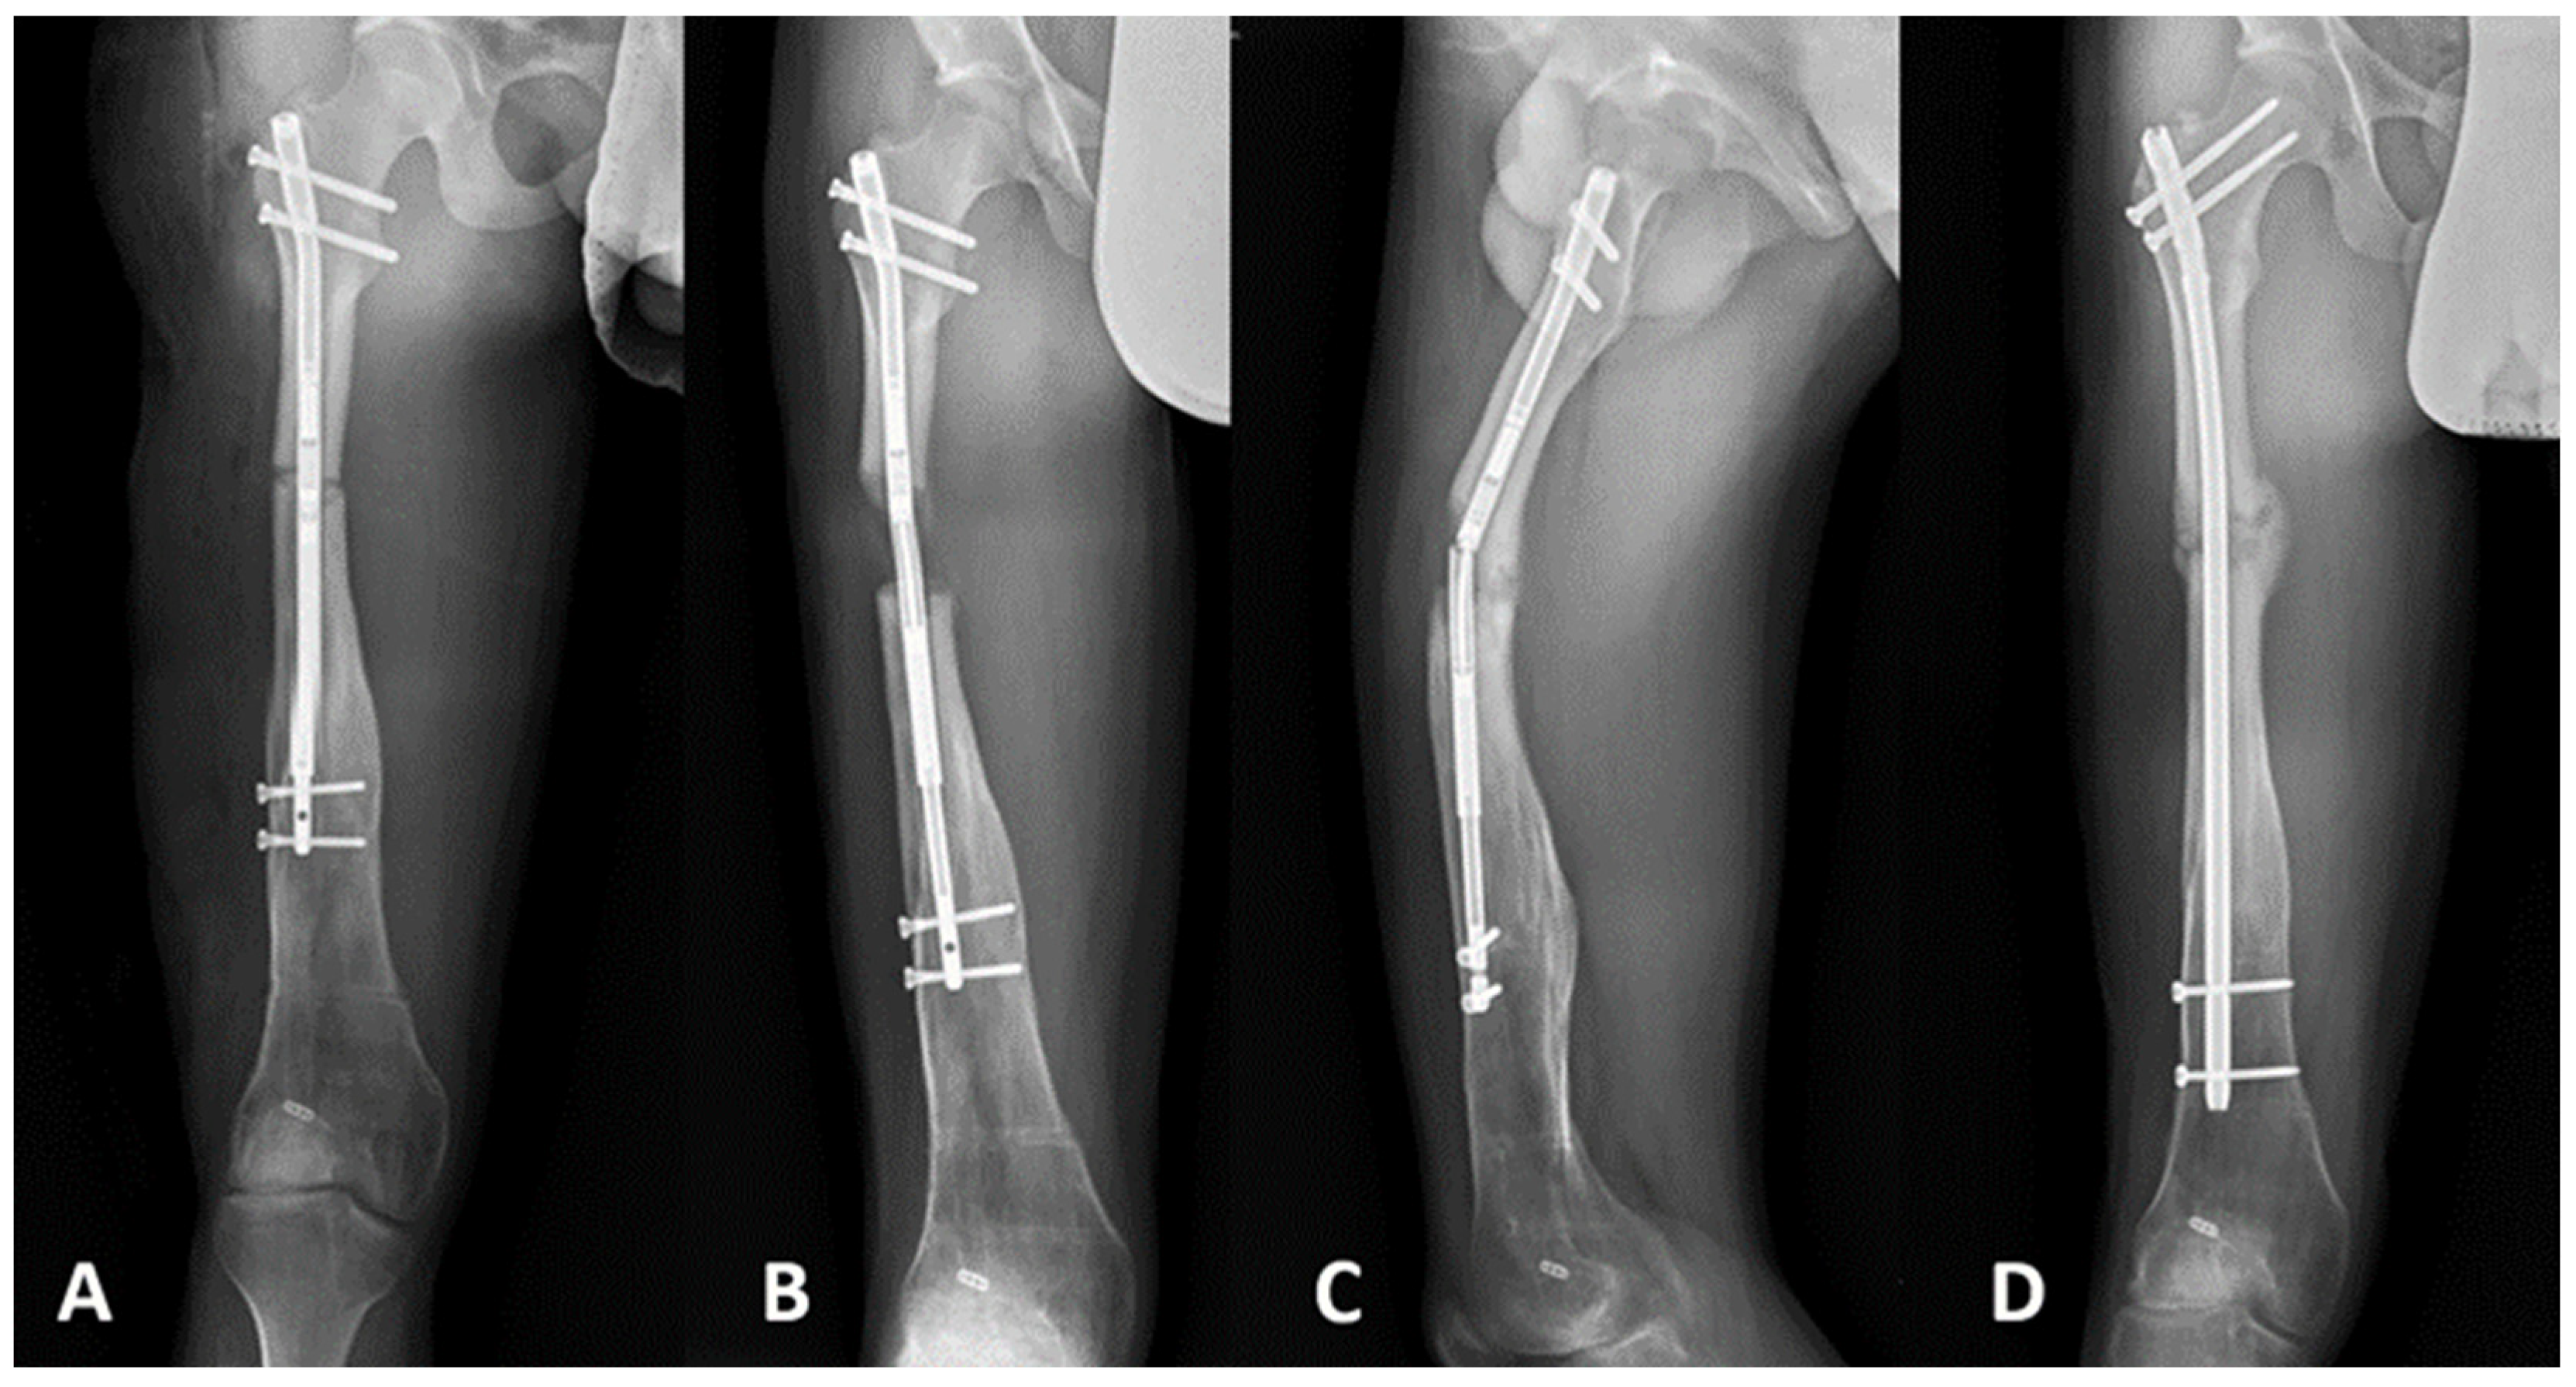

| Complications | 1 (9%)—hardware failure (broken nail and regenerate fracture) (Figure 2) | 1 (9%)—malunion 1 (9%)—fracture post removal (Figure 3) | 2 (12%)—fracture post removal |